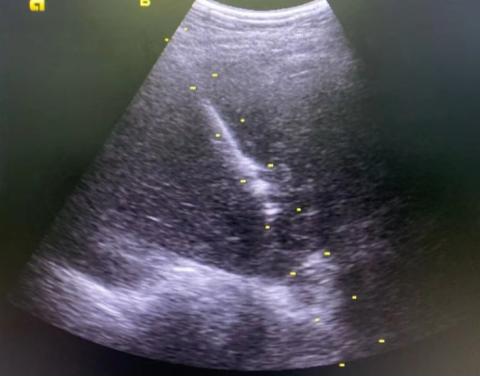

B超引导下肝肿物穿刺活检